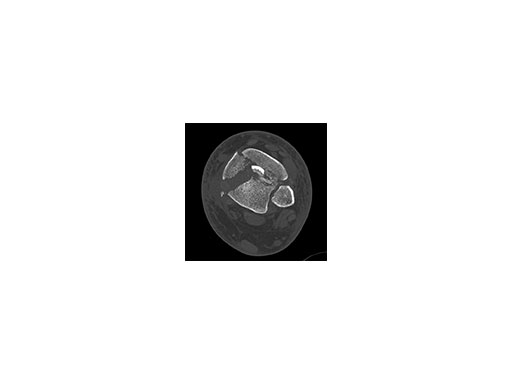

A 45-year-old patient fell from his horse, receiving a closed bimalleolar fracture/ dislocation (Fig 10). Computed tomorgraphy demonstrated an additional anterolateral avulsion injury and syndesmosis dislocation. Osteosynthesis was conducted with a VA-LCP Lateral Distal Fibula Plate.